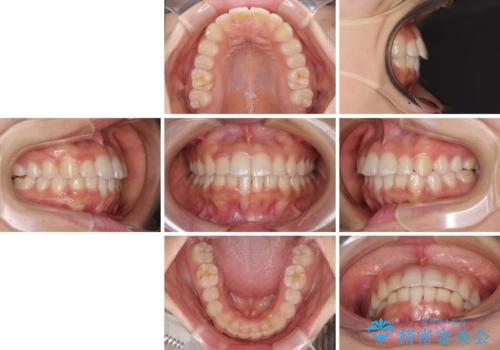

大きなトラブルもなく、順調に歯列が整ったため、僅か9ヶ月で装置を外すことができました。

あまりに短期間であったため、患者様自身も非常に驚いていらっしゃいました。